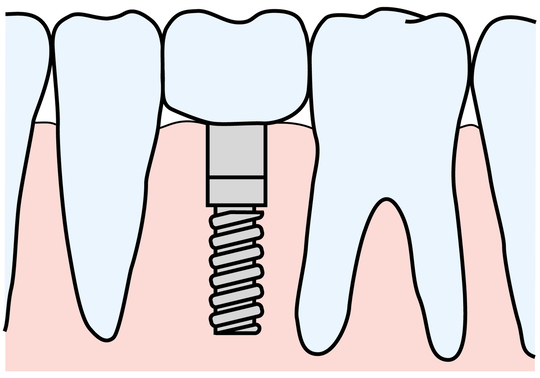

インプラント

天然歯とインプラントの断面

人間の歯はサメのように何度も生え変わりをすることはありません。つまり永久歯は一度抜けると二度と生えてきません。抜歯後には、ブリッジ・入れ歯・インプラントという方法がとられるのが一般的です。どの方法も一長一短ですが、すべてに共通するのが『抜歯が前提であり、歯根膜が失われた状態での修復である』ということです。

『歯根膜』は、歯根の保護や周囲組織への栄養や、噛む力を受け止めるクッションの役割など、200~300ミクロンという薄さながら大きな役割をいくつも持っています。また、歯根膜から脳への直接の信号を噛むたびに送ることで、ボケ防止にも役に立っているといわれています。(歯が多い高齢者はボケにくい。)

親知らずを抜歯箇所に移植するのは、他の3つの方法に比べて制限はあるものの、歯根膜を得ることができるということで大きな意味があります。また、前後の歯を削ったり、負荷をかけるブリッジや入れ歯に代わる方法として保険が利くのも魅力です。(保険がきかない場合もあります)予後が読みにくく、多少不確定要素もありますが、上記3つの方法加えて、第4の方法となります。